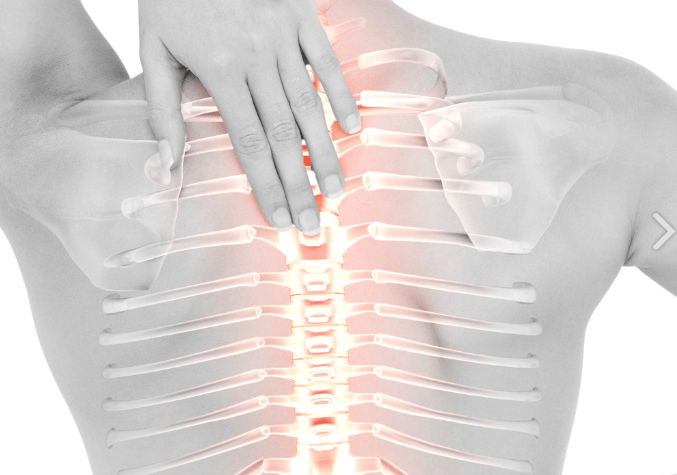

오십견은 어깨 관절을 싸고 있는 관절낭에 염증이 생겨, 일상생활에서 움직이는 범위만큼 움직이지 않는 질환입니다.

오십견은 견관절 부위에서 발생하는 통증과 운동 제한을 동반한 상태로, 외상 없이 또는 경미한 외상 이후에 나타날 수 있습니다. 주로 50대 이후에 발생하며 특발성인 경우에는 원인을 알 수 없습니다.

환자들은 동통, 야간통, 그리고 운동 제한과 같은 증상을 겪게 됩니다.

1) 야간통은 특히 누워 있는 자세에서 더욱 심해져 수면 장애를 유발할 수 있습니다. 이러한 증상은 다른 어깨 질환에서도 나타날 수 있어 동결견과는 구별이 필요합니다. 관절 운동은 전방 거상, 외전, 외회전, 내회전이 모두 제한되며, 서서히 진행하여 환자의 일상 생활이 불편해지게 됩니다.